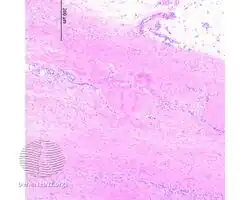

Additional images

Eosinophilic fasciitis/pathology